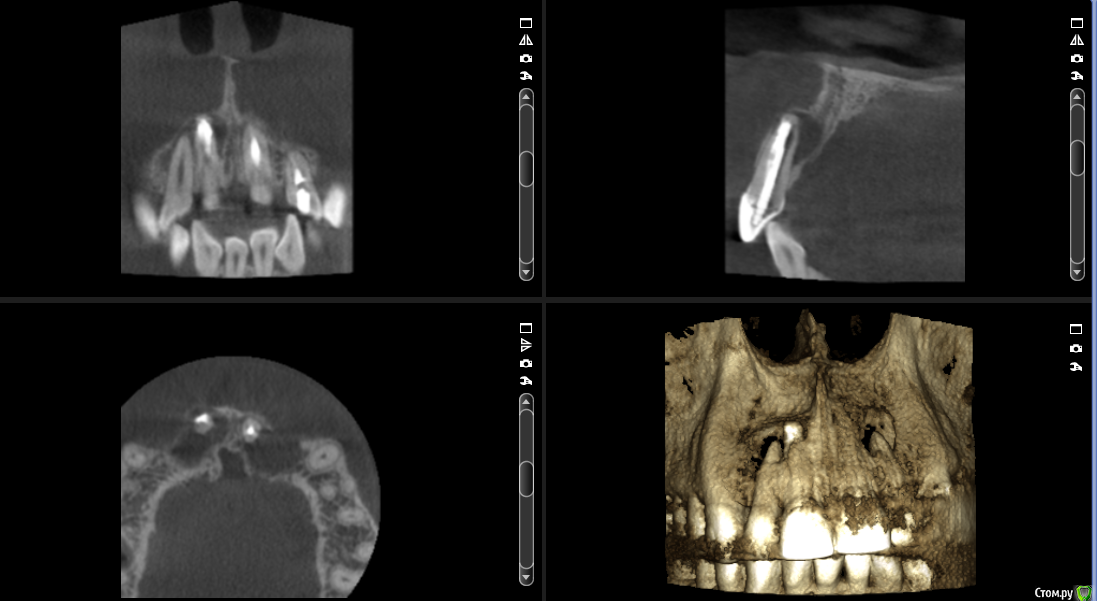

___49___ Опубликовано 5 декабря, 2016 Поделиться Опубликовано 5 декабря, 2016 Что скажите коллеги - интересно ваше мнение , советы. 11 зуб - канал разбит - пока не решил, что с ним делать. Остальные зубы однозначно хочу оставить + эндо 12 му. А после резекция..... Ссылка на комментарий

___49___ Опубликовано 5 декабря, 2016 Автор Поделиться Опубликовано 5 декабря, 2016 Я бы удалил, стенки тонкие,может треснуть ,канал переобработан,сложно хорошо вычистить и добиться апикальной герметичности ,да изуб не стратегически важный, на план лечения влияет не сильно.А если заретроградить ? убрав часть разбитого апекса? Ссылка на комментарий

Евгений Ходыкин Опубликовано 5 декабря, 2016 Поделиться Опубликовано 5 декабря, 2016 Пробуйте ортоградно. МТА в помощь... 2 Ссылка на комментарий

___49___ Опубликовано 5 декабря, 2016 Автор Поделиться Опубликовано 5 декабря, 2016 Пробуйте ортоградно. МТА в помощь...Опешите пожалуйста подробней как вы бы это выполнили ? я думаю - канал ортоградно перелечить в 11 , эндо в 12 и после резекцию с ретроградкой МТА. Ссылка на комментарий

Евгений Ходыкин Опубликовано 6 декабря, 2016 Поделиться Опубликовано 6 декабря, 2016 Опешите пожалуйста подробней как вы бы это выполнили ? я думаю - канал ортоградно перелечить в 11 , эндо в 12 и после резекцию с ретроградкой МТА.При таких "разбитых" апексах всё отмываете, апексифицируете МТА. Выше можно и гутту. Ничего по не резецировать. Сделайте КТ через год, там и оцениваете результат... Ссылка на комментарий